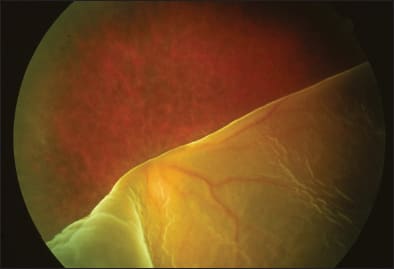

John T. Thompson, MD, who is a partner with Retina Specialists in Frederick, MD, gave a presentation on the detection and repair of giant retinal tears. While most giant retinal tears, Dr. Thompson began, quickly lead to retinal detachment (Figure 9), patients occasionally present before detachment has occurred. Tears such as these should be treated with at least two to three rows of laser photocoagulation. Then the patients should be monitored carefully for extension of the tear or RD.

Figure 9. Most giant retinal tears quickly lead to retinal detachment.